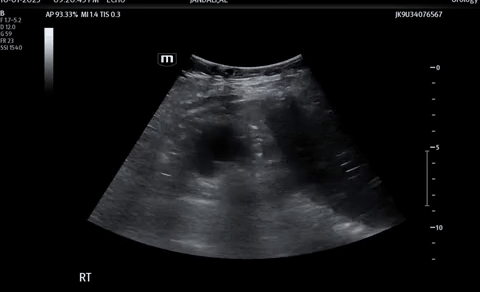

A 70 year old male presenting with worsening right flank pain over the last two days.

Ultrasound of his right kidney revealed…

Bedside POCUS

A renal/bladder POCUS was performed to evaluate for any secondary signs of obstruction.

These images demonstrate severe hydronephrosis with obvious loss of renal architecture.